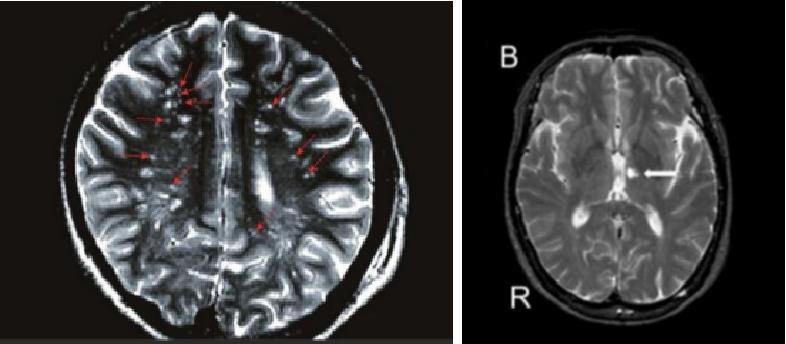

事实上,“腔隙性缺血灶”或“腔隙性梗死”只是一个影像学表现,并不一定等同于真正意义上的脑梗死。若没有典型症状,甚至无症状时,这些影像学表现被统称为“无症状性脑血管病”。

(3) “无症状的”, 指症状和影像学改变不匹配的,这些常见一些年轻人,没有中风症状及血管病高危因素的患者,可能只是单纯的偏头痛、睡眠不好、焦虑抑郁的症状,做检查时顺带发现。